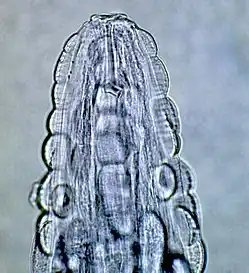

Gongylonema pulchrum

- Gongylonema pulchrum Molin, 1857